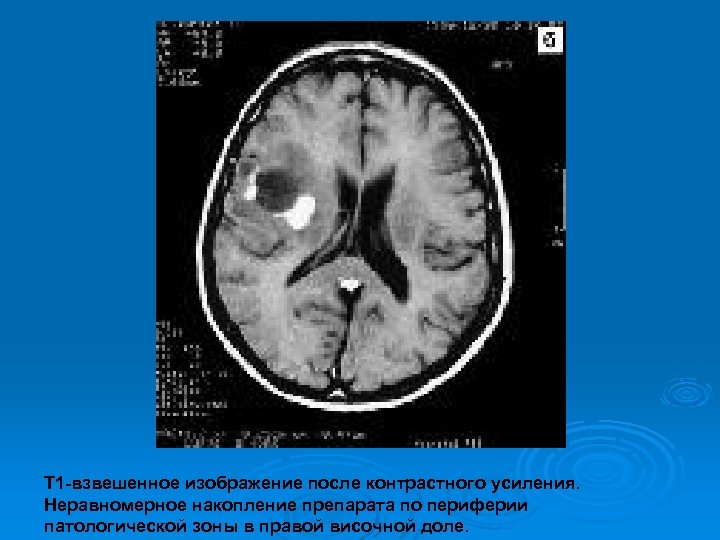

Изменения МРТ на фоне гормональной терапии

Т 1 -взвешенное изображение после контрастного усиления. Неравномерное накопление препарата по периферии патологической зоны в правой височной доле.